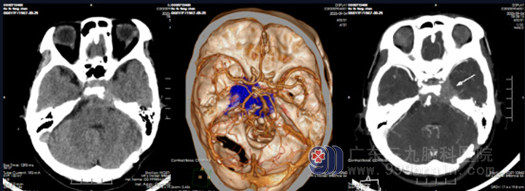

图 2 头部CTA检查示:鞍内-左侧鞍旁-岩斜区-斜坡后方-蝶窦稍高密度占位性病变,病变内可见些许细小血管影,病变包绕左侧颈内动脉C3-C4段、双侧椎动脉末端基底动脉,邻近骨质密度增高。